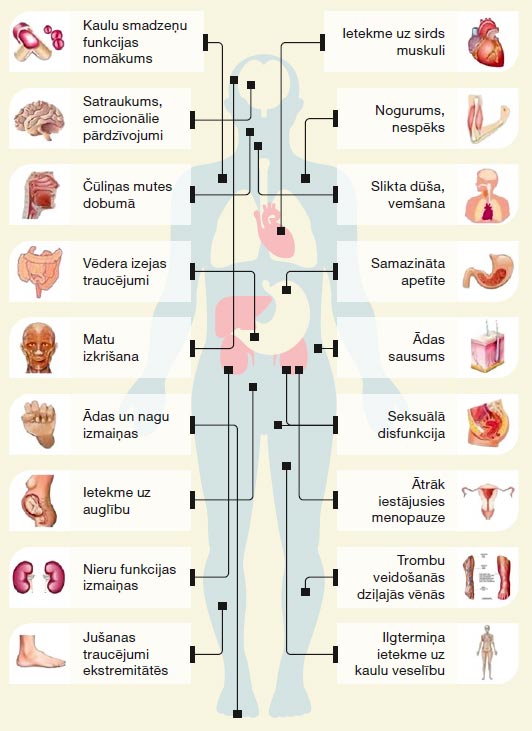

Pirms katras ķīmijterapijas ievades pacients vēnā saņem zāles pret alerģiju un sliktu dūšu. Šie medikamenti var izraisīt miegainību, tāpēc ķīmijterapijas saņemšanas dienā nerekomendē vadīt automašīnu un ir vēlams būt tuvinieka pavadībā, dodoties mājās. Ķīmijterapija visātrāk un visintensīvāk uzkrājas vēža šūnās, jo tās ātrāk aug un vairojas. Tomēr, izplatoties ar asinsriti pa visu organismu, ķīmijterapija ietekmē arī veselos audus ar aktīviem vielmaiņas procesiem – kaulu smadzeņu šūnas, gremošanas traktu izklājošās šūnas, matu folikulu šūnas, dzimumšūnas. Ietekme uz šīm šūnām nosaka ķīmijterapijas blakņu profilu. Tikai 5–10 % pacientu rodas nopietnas blaknes, kuru ārstēšana notiek slimnīcas stacionārā. Ķīmijterapijas blaknes pāriet dažu dienu līdz mēnešu laikā pēc ķīmijterapijas pabeigšanas, un tikai neliela daļa var būt paliekošas. Biežākās blaknes ir nogurums, slikta dūša un vemšana dažas dienas pēc ķīmijterapijas, apetītes izmaiņas, vēdera izejas traucējumi, dažādas intensitātes matu izkrišana, anēmija, infekcijas risks.

Iespējamās ķīmijterapijas blakusparādības.

Pretēji citotoksiskai ķīmijterapijai imūnterapija stimulē, nevis nomāc organisma imunitāti, tāpēc arī imūnterapijas blakusparādības ir saistītas nevis ar imunitātes novājināšanu, bet ar tās stimulāciju. Imunitātes stimulācija var notikt ne tikai pret vēža šūnām, bet arī pret organisma normālām šūnām. Tas izpaužas kā iekaisums, ko organisms izraisa pats pret sevi: ādas iekaisums (dermatīts), locītavu iekaisums (artrīts), vairogdziedzera iekaisums (tireoidīts), zarnu iekaisums (kolīts), plaušu iekaisums (pneimonīts) u.c. (skat. tabulu) Imūnterapijas blakusparādības, ja parādās, tad visbiežāk pirmo trīs mēnešu laikā no terapijas sākuma. Blakusparādības iedala smaguma pakāpēs, un visbiežāk novēro viegli- vidēji izteiktas blakusparādības. Tās ir labi ārstējamas ar kortikosteoīdiem – pretiekaisuma medikamentiem tablešu vai injekciju veidā.

Līdzīgi kā citotoksiskās ķīmijterapijas medikamenti, arī mērķterapija var izraisīt blaknes – sliktu dūšu, vēdera izejas traucējumus, ādas un nagu izmaiņas, izmaiņas asins analīzēs. Atkarībā no izteiktības un ietekmes uz pacienta dzīves kvalitāti blaknes iedala smaguma pakāpēs. Blaknes ir ārstējamas un lielai daļai pacientu ārstēšana ar mērķterapiju norit bez izteiktām komplikācijām.

Pretēji citotoksiskai ķīmijterapijai imūnterapija stimulē, nevis nomāc organisma imunitāti, tāpēc arī imūnterapijas blakusparādības ir saistītas nevis ar imunitātes novājināšanu, bet ar tās stimulāciju. Imunitātes stimulācija var notikt ne tikai pret vēža šūnām, bet arī pret organisma normālām šūnām. Tas izpaužas kā iekaisums, ko organisms izraisa pats pret sevi: ādas iekaisums (dermatīts), locītavu iekaisums (artrīts), vairogdziedzera iekaisums (tireoidīts), zarnu iekaisums (kolīts), plaušu iekaisums (pneimonīts) u.c. (skat. tabulu) Imūnterapijas blakusparādības, ja parādās, tad visbiežāk pirmo trīs mēnešu laikā no terapijas sākuma. Blakusparādības iedala smaguma pakāpēs, un visbiežāk novēro viegli- vidēji izteiktas blakusparādības. Tās ir labi ārstējamas ar kortikosteoīdiem – pretiekaisuma medikamentiem tablešu vai injekciju veidā.